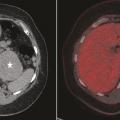

TEP-scan au 18-FDG

La tomographie par émission de positons couplée à un scanner (TEP-scan) au 18-FDG (traceur dérivé du glucose marqué avec une molécule de fluor 18) est un examen de deuxième intention. Une hyperfixation y traduit l’avidité métabolique du tissu néoplasique. Surtout, une absence de fixation de l’incidentalome a une valeur d’exclusion de la malignité de plus de 90 % (Calcul du wash out

fig. 3 ).5 Si la valeur prédictive négative de la TEP est donc un argument fort en faveur de la bénignité, une augmentation de la captation du FDG n’est cependant pas spécifique et peut également s’observer, essentiellement en cas de phéochromocytome bénin mais aussi dans certains adénomes corticaux bénins ou hémorragies surrénaliennes, notamment.